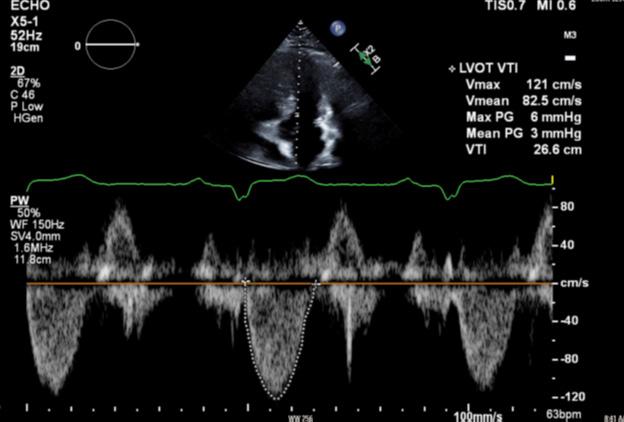

• El ecocardiograma realizado para evaluar la función y las estructuras cardíacas, reveló fracción de eyección conservada, engrosamiento del tabique interventricular de 2,9 cm y gradiente del TSVI de 48 mmHg.

• La visita de seguimiento a las 8 semanas de su inicio demostró síntomas mejorados consistentes con la clase I de la NYHA, ausencia de soplos audibles y evidencia de reducción del gradiente del TSVI a 7 mmHg.

Figure 4: Deformación miocárdica longitudinal del ecocardiograma basal. Figure 5: Ecocardiograma 8 semanas después del uso de Mavacamten que muestra un gradiente en el TSVI reducción de 48 mmHg a 7 mmHg. Figure 6:Ecocardiograma 12 semanas después del uso de Mavacamten que muestra una continua reducción del gradiente del TSVI a 3 mmHg.